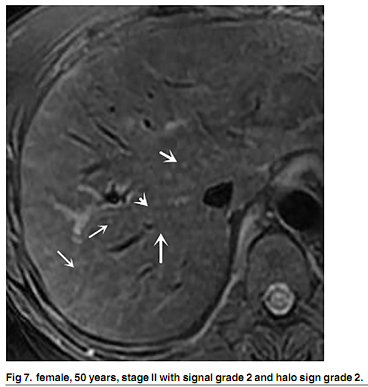

MRI显示,25例患者呈门静脉周围高信号,8例呈I期和II期均匀肝脏信号强度,以及25例呈非均质肝脏信号变化。组织学分级和肝脏信号强度不一致之间存在正相关(P <0.001)。

4种组织学分析的门静脉周围晕征存在差异(P = 0.034),门静脉周围晕征与组织学分级之间呈正相关(P <0.001)4个组织学分期与淋巴结肿大及肿大的淋巴结的大小之间未见差异。

“MRI可可靠的检测PBC一般指征,如肝肿大,脾肿大,门静脉主干扩张,门脉侧支循环和腹水,”研究人员得出结论称。“MRI是诊断PBC的一种有价值的方法,门脉周围晕征程度和肝脏信号强度有助于评估肝纤维化程度。” - Melinda Stevens